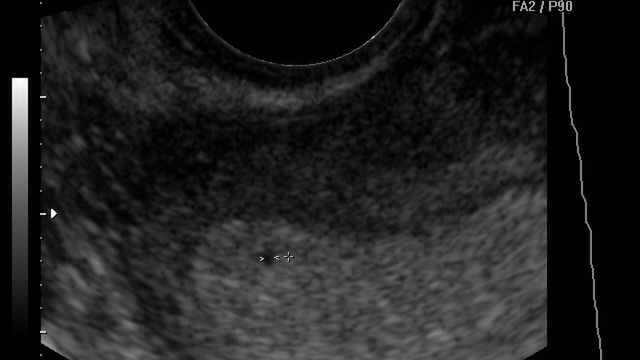

Płód w 4 tygodniu ciąży

W 4 tygodniu widać główkę dziecka, na której wyróżnić można jamę ustną, dodatkowo zaczyna pracować serce. Bije od 21 dnia ciąży.

/ 1Płód w 4 tygodniu ciąży - wielkość płodu

Pod koniec 4 tygodnia dziecko jest wielkości porównywalnej do ziarenka ryżu.